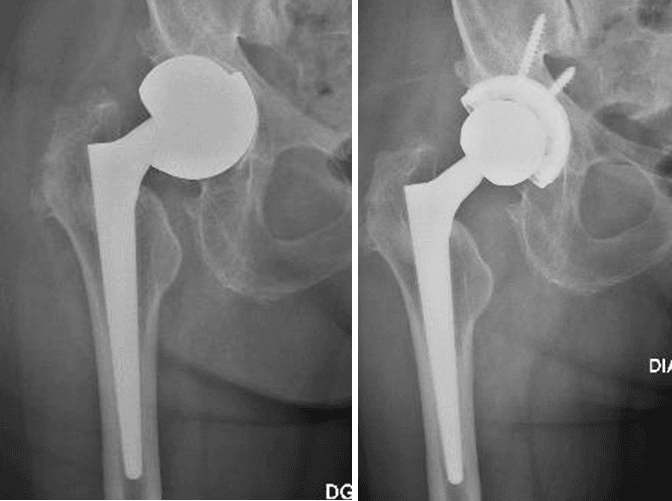

L’intervento chirurgico di revisione protesica si attua nel caso di fallimento dell’impianto primario. La revisione può essere totale (quando vengono sostituite tutte le componenti) o parziale (quando vengono sostituite solo alcune componenti), a seconda dell’entità e del tipo di problema riscontrato.

La revisione protesica rappresenta una vera e propria sfida per il Chirurgo Ortopedico, soprattutto in quei casi gravati da importante perdita del bone stock, da deficit dei tessuti molli periarticolari o in presenza di alterazioni del trofismo cutaneo, talvolta con perdita severa di sostanza, in esiti di plurimi interventi chirurgici.

L’esperienza e l’approccio del nostro centro

Grazie ad un’esperienza chirurgica decennale nel trattamento e nella gestione di casi difficili di revisione protesica, presso il nostro centro di Chirurgia Protesica pianifichiamo accuratamente gli interventi ricostruttivi protesici, avvalendoci delle più innovative tecniche e metodiche chirurgiche (impianti protesici su misura quando necessari), ponendo particolare attenzione nell’utilizzo di materiali protesici biocompatibili che garantiscono un’ottimale osteointegrazione ed una resistenza all’usura sempre maggiore.